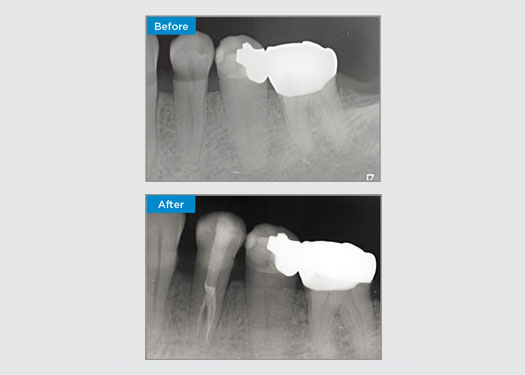

Le patient s’est présenté avec une parodontite apicale asymptomatique sur la dent 34. Sur la radiographie préopératoire, la dent 34 présentait deux racines visibles. Cependant, un balayage CBCT a confirmé qu’il s’agissait d’une prémolaire à trois racines et que les canaux se divisaient en trois au milieu de la racine. Une sélection minutieuse des limes est essentielle pour cette dent délicate.

Dr Jack Lin, Endodontiste, Sydney, NSW Australie

Dans cette situation, la préservation de la structure de la dent/racine est essentielle pour réduire le risque de déviation, de déplacement, de fermeture, de perforation et de fracture de la racine. La sélection des cas, le diagnostic et la planification du traitement préalable sont importants. Le choix de la lime endodontique en fonction de sa flexibilité, de son efficacité et du respect de l’anatomie naturelle de la racine est essentiel.